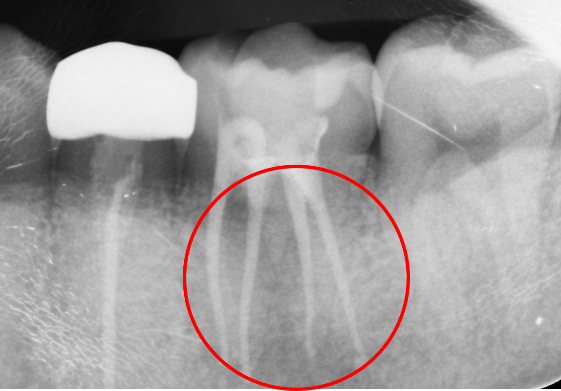

1年後

1年後のレントゲンでは、根尖の病変がなくなり、骨ができています。